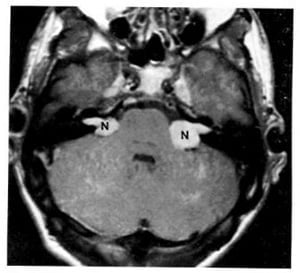

Hình 1.62. U thần kinh thính giác hai bên bắt mạnh chất cản quang ở một bệnh nhân có bệnh u xơ thần kinh loại 2.

1.7. U thần kinh (u bao Schwann) (Hình 1.61, 1.62)

Dấu hiệu XQCTĐT:

– Rất thường xảy ra ở thần kinh thính giác và khu trú ở góc cầu tiểu não.

– Trừ khi hoại tử, nó thường có mật độ ngang và bắt chất cản quang rõ.

Chú giải:

– Trong bệnh u xơ thần kinh loại 2, hai u bao Schwann có thể nối tiếp nhau sau nhiều năm hoặc có thể xảy ra đồng thời.